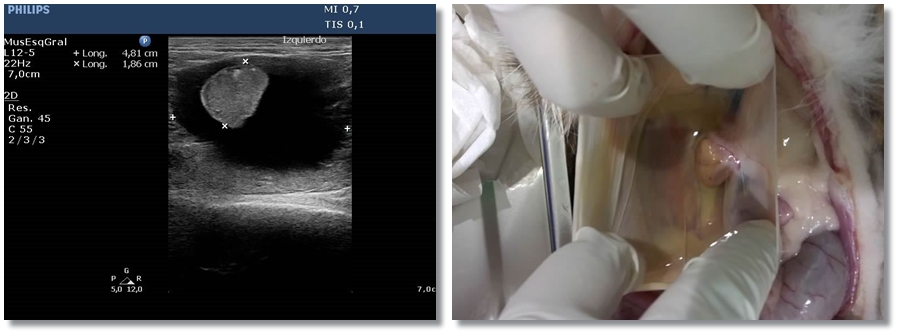

Tumor ectópico de tiroides o hemangiosarcoma Radiografía/Ecografía Bóxer de 11 años que presenta pérdida de…

Hembra fértil con cojera en EPI y abdomen en tabla. Se realiza estudio ecográfico y…